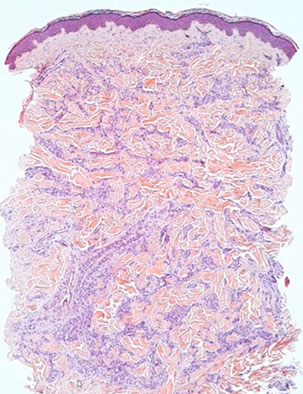

Kaposi sarcoma

Low grade endothelial malignancy that can be classic or AIDS assoc

- hyperhcromatic spindle cells c vascular slit pattern and extravasated RBCs

- HHV-8 plays role in all subtypes

Micro: spindle cells forming slits c extravasated RBCs, hemosiderin laden macrophages, lymphs and fibrosis

- minimal atypia

- can have lots of PAS+ hyaline bodies, which are heme breakdown products

- moderate mits

Stages: Early-patch, later-plaque tumor, and nodular

- also a lymphanioma-like variant with thin, angulated vessels with no RBCs

Early-patch - bizarre staghorn vessels and plasma cells

Later-plaque - busy dermis surrounding adnexal structures and vessels

- Promontory sign - protrusion of pre-existing structues into lake-like ectatic space, leaves vessels looking like they are floating in space

Nodular - fascicles of spindle cells, separated by slit-like vascular spaces containing erythrocytes, PAS positive diastase resistant hyaline globules, extravasated RBCs, scattered plasma cells, and hemosiderin deposits

IHC: (+) CD34>CD31, factor VIII related antigen, podoplanin (D2-40), LANA (very sensitive and specific for HHV-8 infx)

Kaposi sarcoma - early patch stage

Kaposi sarcoma, nodular stage